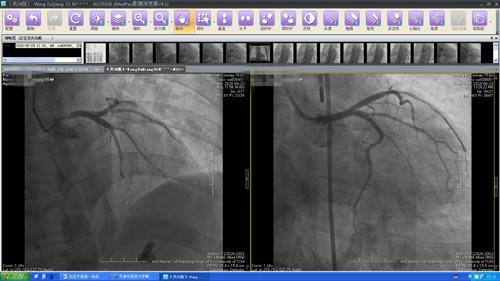

病例一,男性,59岁,主因“胸痛3小时”由120送至华人策略急诊,急诊医师接诊后考虑“急性ST段抬高型心肌梗死”,床旁超声提示心脏功能极差,呼叫心血管科值班医师会诊,心血管科王贤良主任了解病情后,深夜紧急启动导管室,绕行CCU行急诊冠脉造影,造影显示左主干体部狭窄85%伴血栓,冠脉三支病变,病情凶险,紧急置入主动脉球囊反搏泵(IABP),无创呼吸机辅助通气,给予冠脉内溶栓,再次造影提示血栓影缩小,心脏功能恢复,考虑病变严重、病情危重,置入支架后血栓有可能进一步脱落影响心肌灌注,不适合立即置入支架,建议病情稳定后再择期介入或行冠脉搭桥治疗,凌晨2点手术顺利结束,患者安全返回CCU,后持续无创通气、漂浮导管监测血流动力学、IABP辅助,患者病情逐渐平稳,2天后患者家属选择转往外院行冠状动脉搭桥术。

图1.2  第一例左主干病变造影及溶栓后造影结果